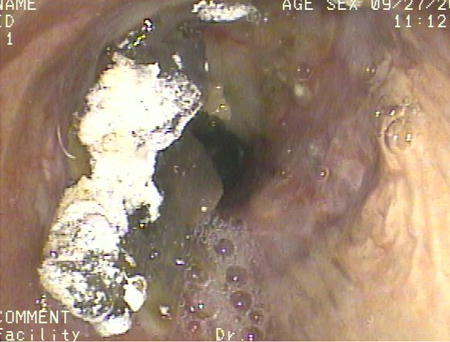

Broncoscopia que muestra la aspiración de bario en el bronquio principal derecho de un paciente sometido a un trasplante de pulmón, tras un estudio con ingesta de solución de bario

De la colección del Dr. Kamran Mahmood